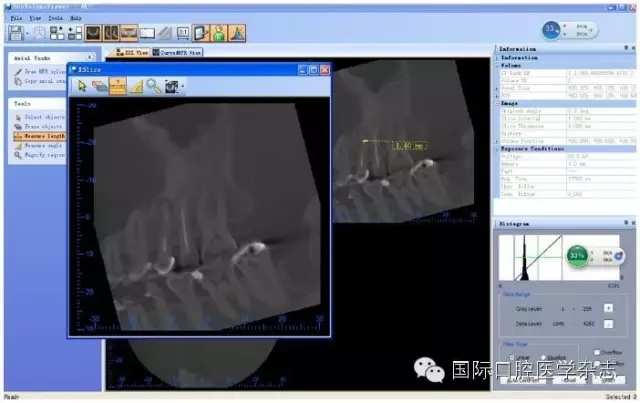

目前,對(duì)于分離器械周圍牙本質(zhì)厚度的評(píng)估以及取出后殘余牙本質(zhì)厚度的預(yù)測主要需借助影像學(xué)檢查,例如根尖片、錐形束CT(cone beamcomputed tomography,CBCT)圖像等。傳統(tǒng)的平行投照的根尖片無法反映三維立體結(jié)構(gòu),且往往存在解剖結(jié)構(gòu)影像的重疊,不利于臨床判斷,具有一定的局限性。多位學(xué)者[10]的研究表明:平行投照的根尖片會(huì)高估實(shí)際的牙本質(zhì)壁的厚度。一些學(xué)者[11-12]的研究表明:當(dāng)分離器械位于上頜第一磨牙近中根管時(shí),采用成角投照(21°)的拍攝技術(shù)與平行投照技術(shù)得到的X線片相比,能更準(zhǔn)確地評(píng)估牙本質(zhì)的厚度,為分離器械取出與否提供指導(dǎo)(圖4)。近年來,CBCT在牙髓病學(xué)中的應(yīng)用越來越廣泛,由于CBCT能清楚地反映牙及牙根周圍組織的三維立體結(jié)構(gòu),為牙本質(zhì)厚度的評(píng)估與預(yù)測提供了可行性(圖5);因此,CBCT在器械分離的病例術(shù)前風(fēng)險(xiǎn)評(píng)估方面具有較好的應(yīng)用前景。

圖 5 使用CBCT評(píng)估分離器械周圍牙本質(zhì)厚度